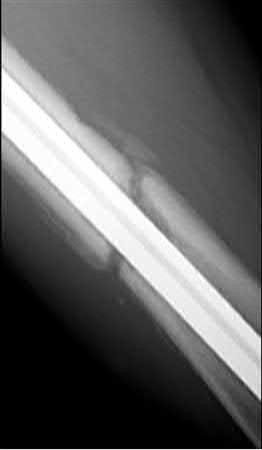

Femoral malrotation after intramedullary nailing is unfortunately a possibility with either antegrade or retrograde nailing techniques. Malrotation and iatrogenic length changes are most common when comminution is present, as cortical reads are inherently limited.

Hufner et al report that malrotation (internal or external >15 degrees) was seen in 22% of their patients via CT scan after intramedullary nailing. There was a significant difference depending on the time of surgery, with significantly more malrotation during the night shift. Increased fracture comminution also significantly increased malrotation rates.